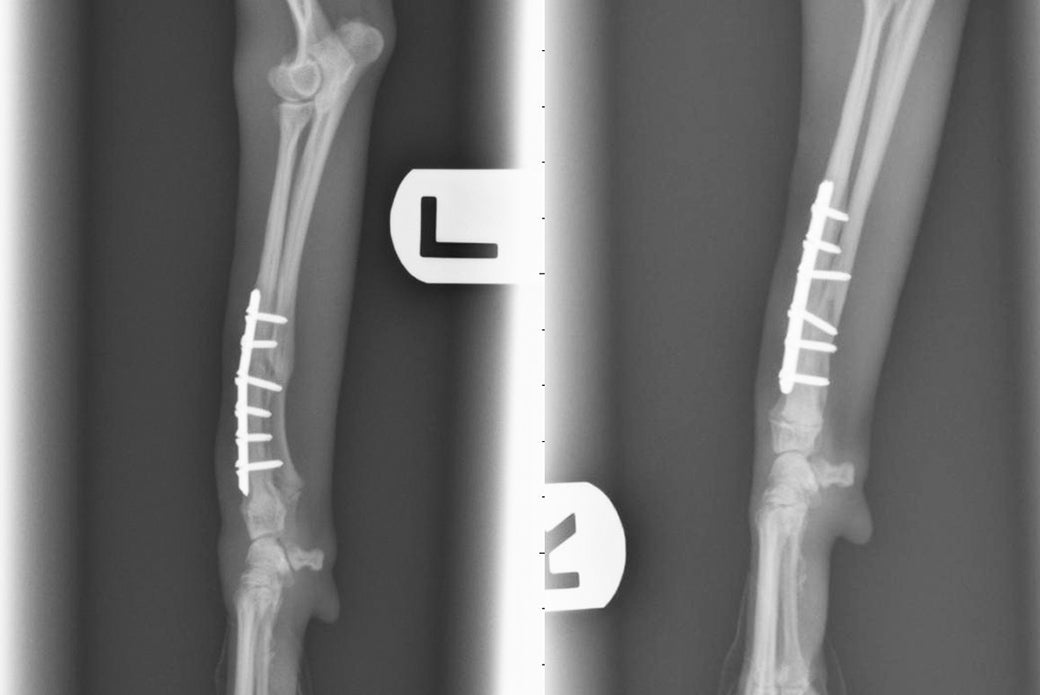

An X-ray of Speedy’s broken legs.

Sadly, what happened to Speedy is not unusual in toy breeds, or dogs weighing less than seven pounds, including Chihuahuas, Yorkshire terriers, and Maltese. “These are common injuries as these dogs tend to jump down from furniture or out of their owner’s arms and then sustain a break,” says ASPCA veterinarian Dr. J’mai Gayle, who repaired Speedy’s legs with bone plates and screws.

Doctors at the ASPCA Animal Hospital were able to repair Speedy’s legs with bone plates and screws.